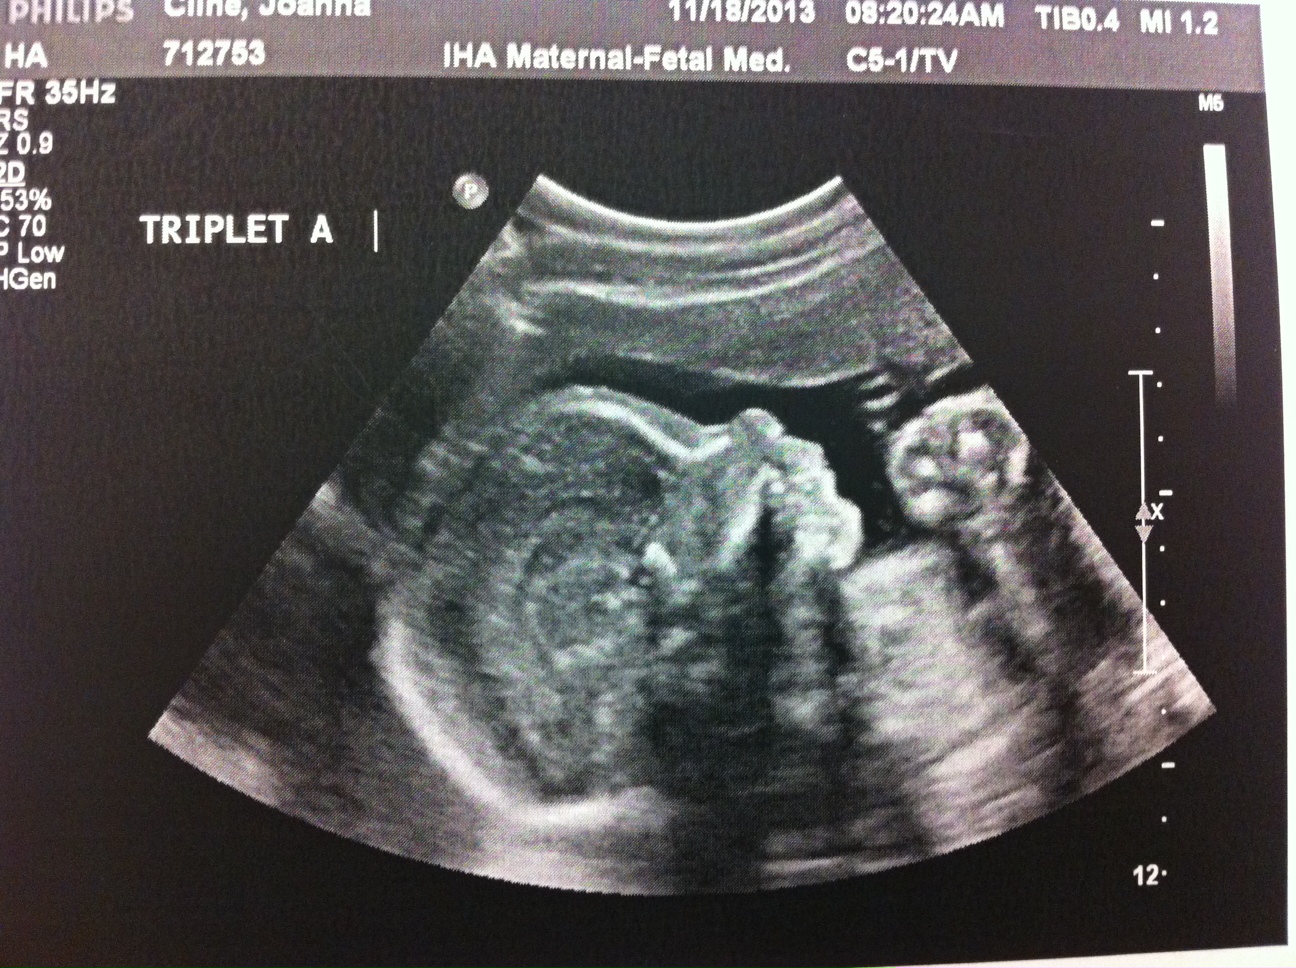

Obviously 24 weeks is still very early (and risky) and we don’t want these babies born yet but it’s still a great checkpoint in my pregnancy. Fortunately, everything looked fantastic at my appointment today. A, B and C looked great and my body is currently a fortress sealing them in where they belong.

Two photos are attached. This week, only A wanted to show his face. And I attached a V Day photo of me. I’m really not sure how my belly is going to get bigger but I’m told it will happen!